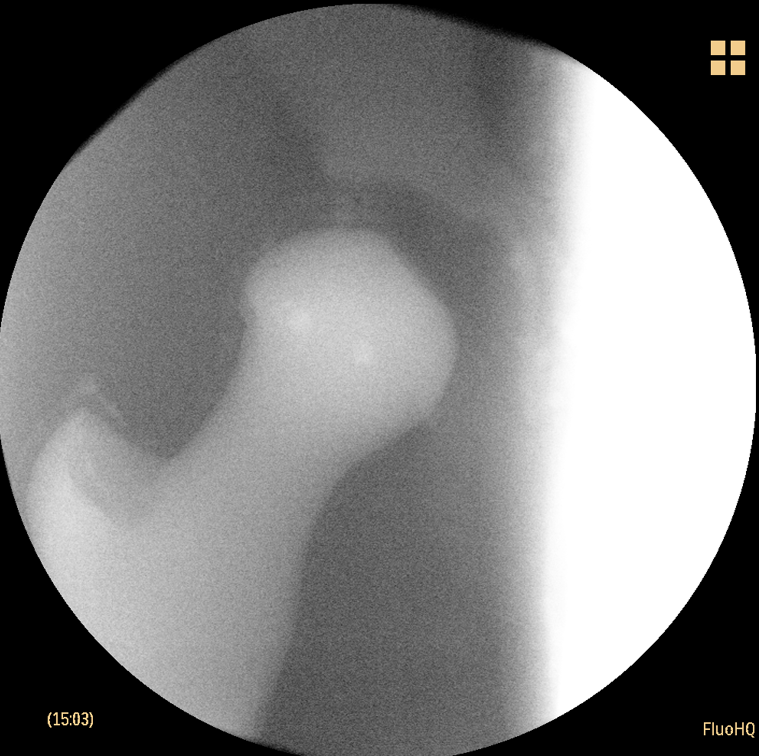

Wir fertigen Phantome für chirurgische Testoperationen / Lehroperationen und zur Validierung von Ultraschallsoftware. Hierbei fokussieren wir uns auf eine Darstellung der Weichtele und der zugehörigen knöchernen Anatomien. Die verwendeten Materialen stellen die Anatomie nicht nur optisch realitätsnah dar, sondern sind auch bezüglich der Haptik, sowie der Bearbeitung (Schneiden, Sägen, Bohren) der Realität nachempfunden. Mit unseren Phantomen können Sie sowohl Schulungsoperationen als auch Testungen von neuartigen Implantaten durchführen und die Ergebnisse mittels Bildgebung kontrollieren.

Bereits realisierte Phantome